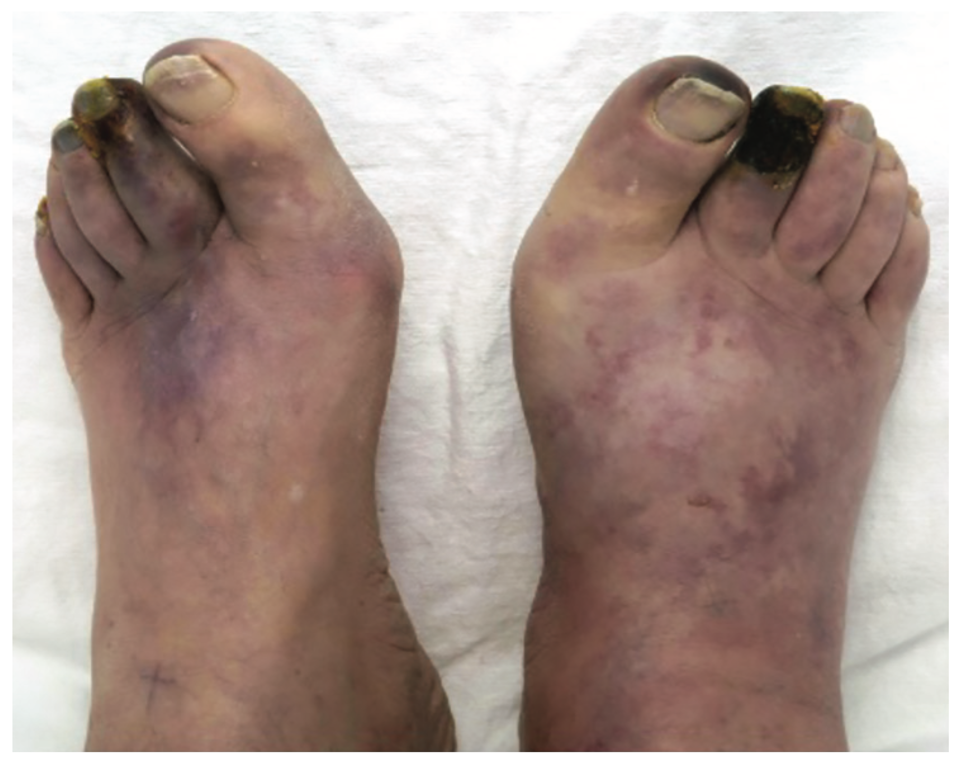

What does this refer to

Progressive severity

asymptomatic

intermittent claudication

pain at rest

nonhealing wounds

ulceration

gangrene and threatened limb

Clinical history of Peripheral Artery Disease (PAD)

What does this refer to

Physical exam peripheral artery disease (PAD)